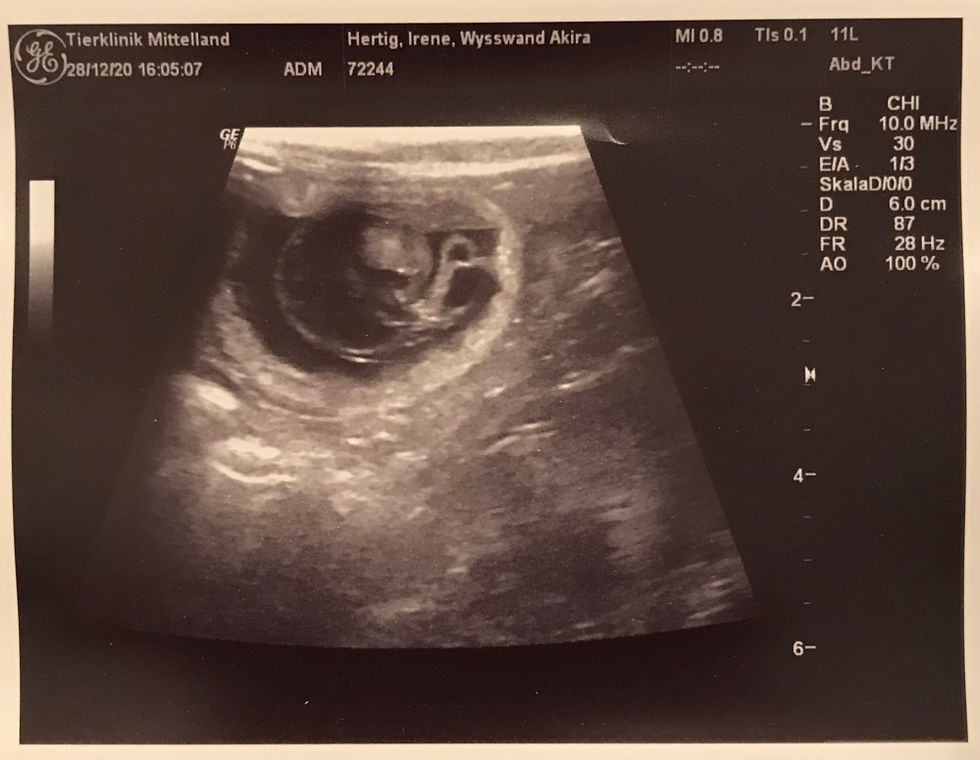

Der Ultraschall hats gezeigt: Akira ist trächtig! Wir freuen uns riesig, in 5 - 6 Wochen wird es soweit sein. Sobald die Kitten dann 8 Wochen alt sind und ihre erste Impfung erhalten haben, freuen wir uns über Besuch!

PS: Die Kitten dieses Wurfs sind alle bereits reserviert.